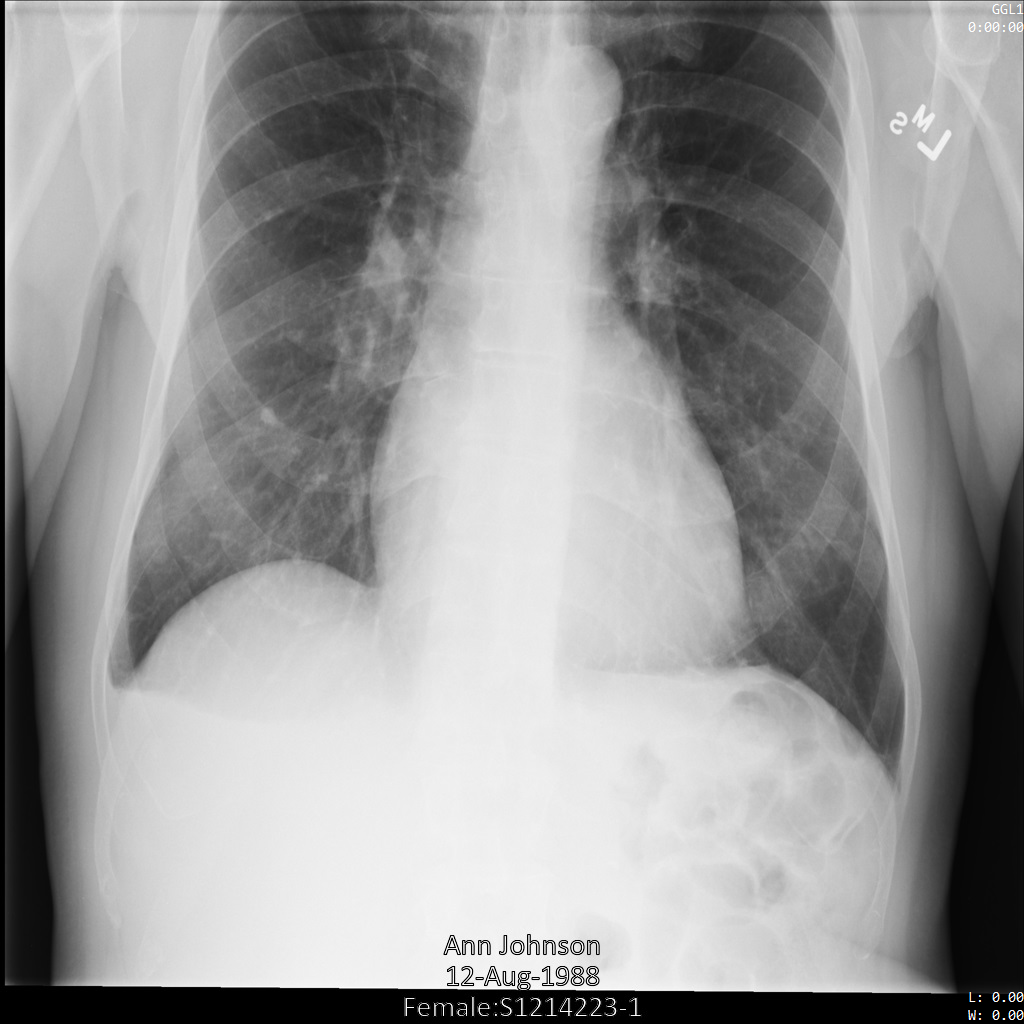

다음 샘플은 데이터 세트의 DICOM 이미지에서 모든 번인 텍스트를 수정하는 방법을 보여줍니다. TextRedactionMode 필드에 REDACT_ALL_TEXT를 지정하면 됩니다.

REDACT_ALL_TEXT 옵션을 사용하여 Cloud Healthcare API에 이미지를 제출하면 이미지가 다음과 같이 표시됩니다. 이미지 하단에 있는 번인 텍스트는 삭제되지만 이미지의 상단 모서리에 있는 메타데이터는 그대로 유지됩니다. 메타데이터도 삭제하려면 DICOM 태그 익명화를 참조하세요.